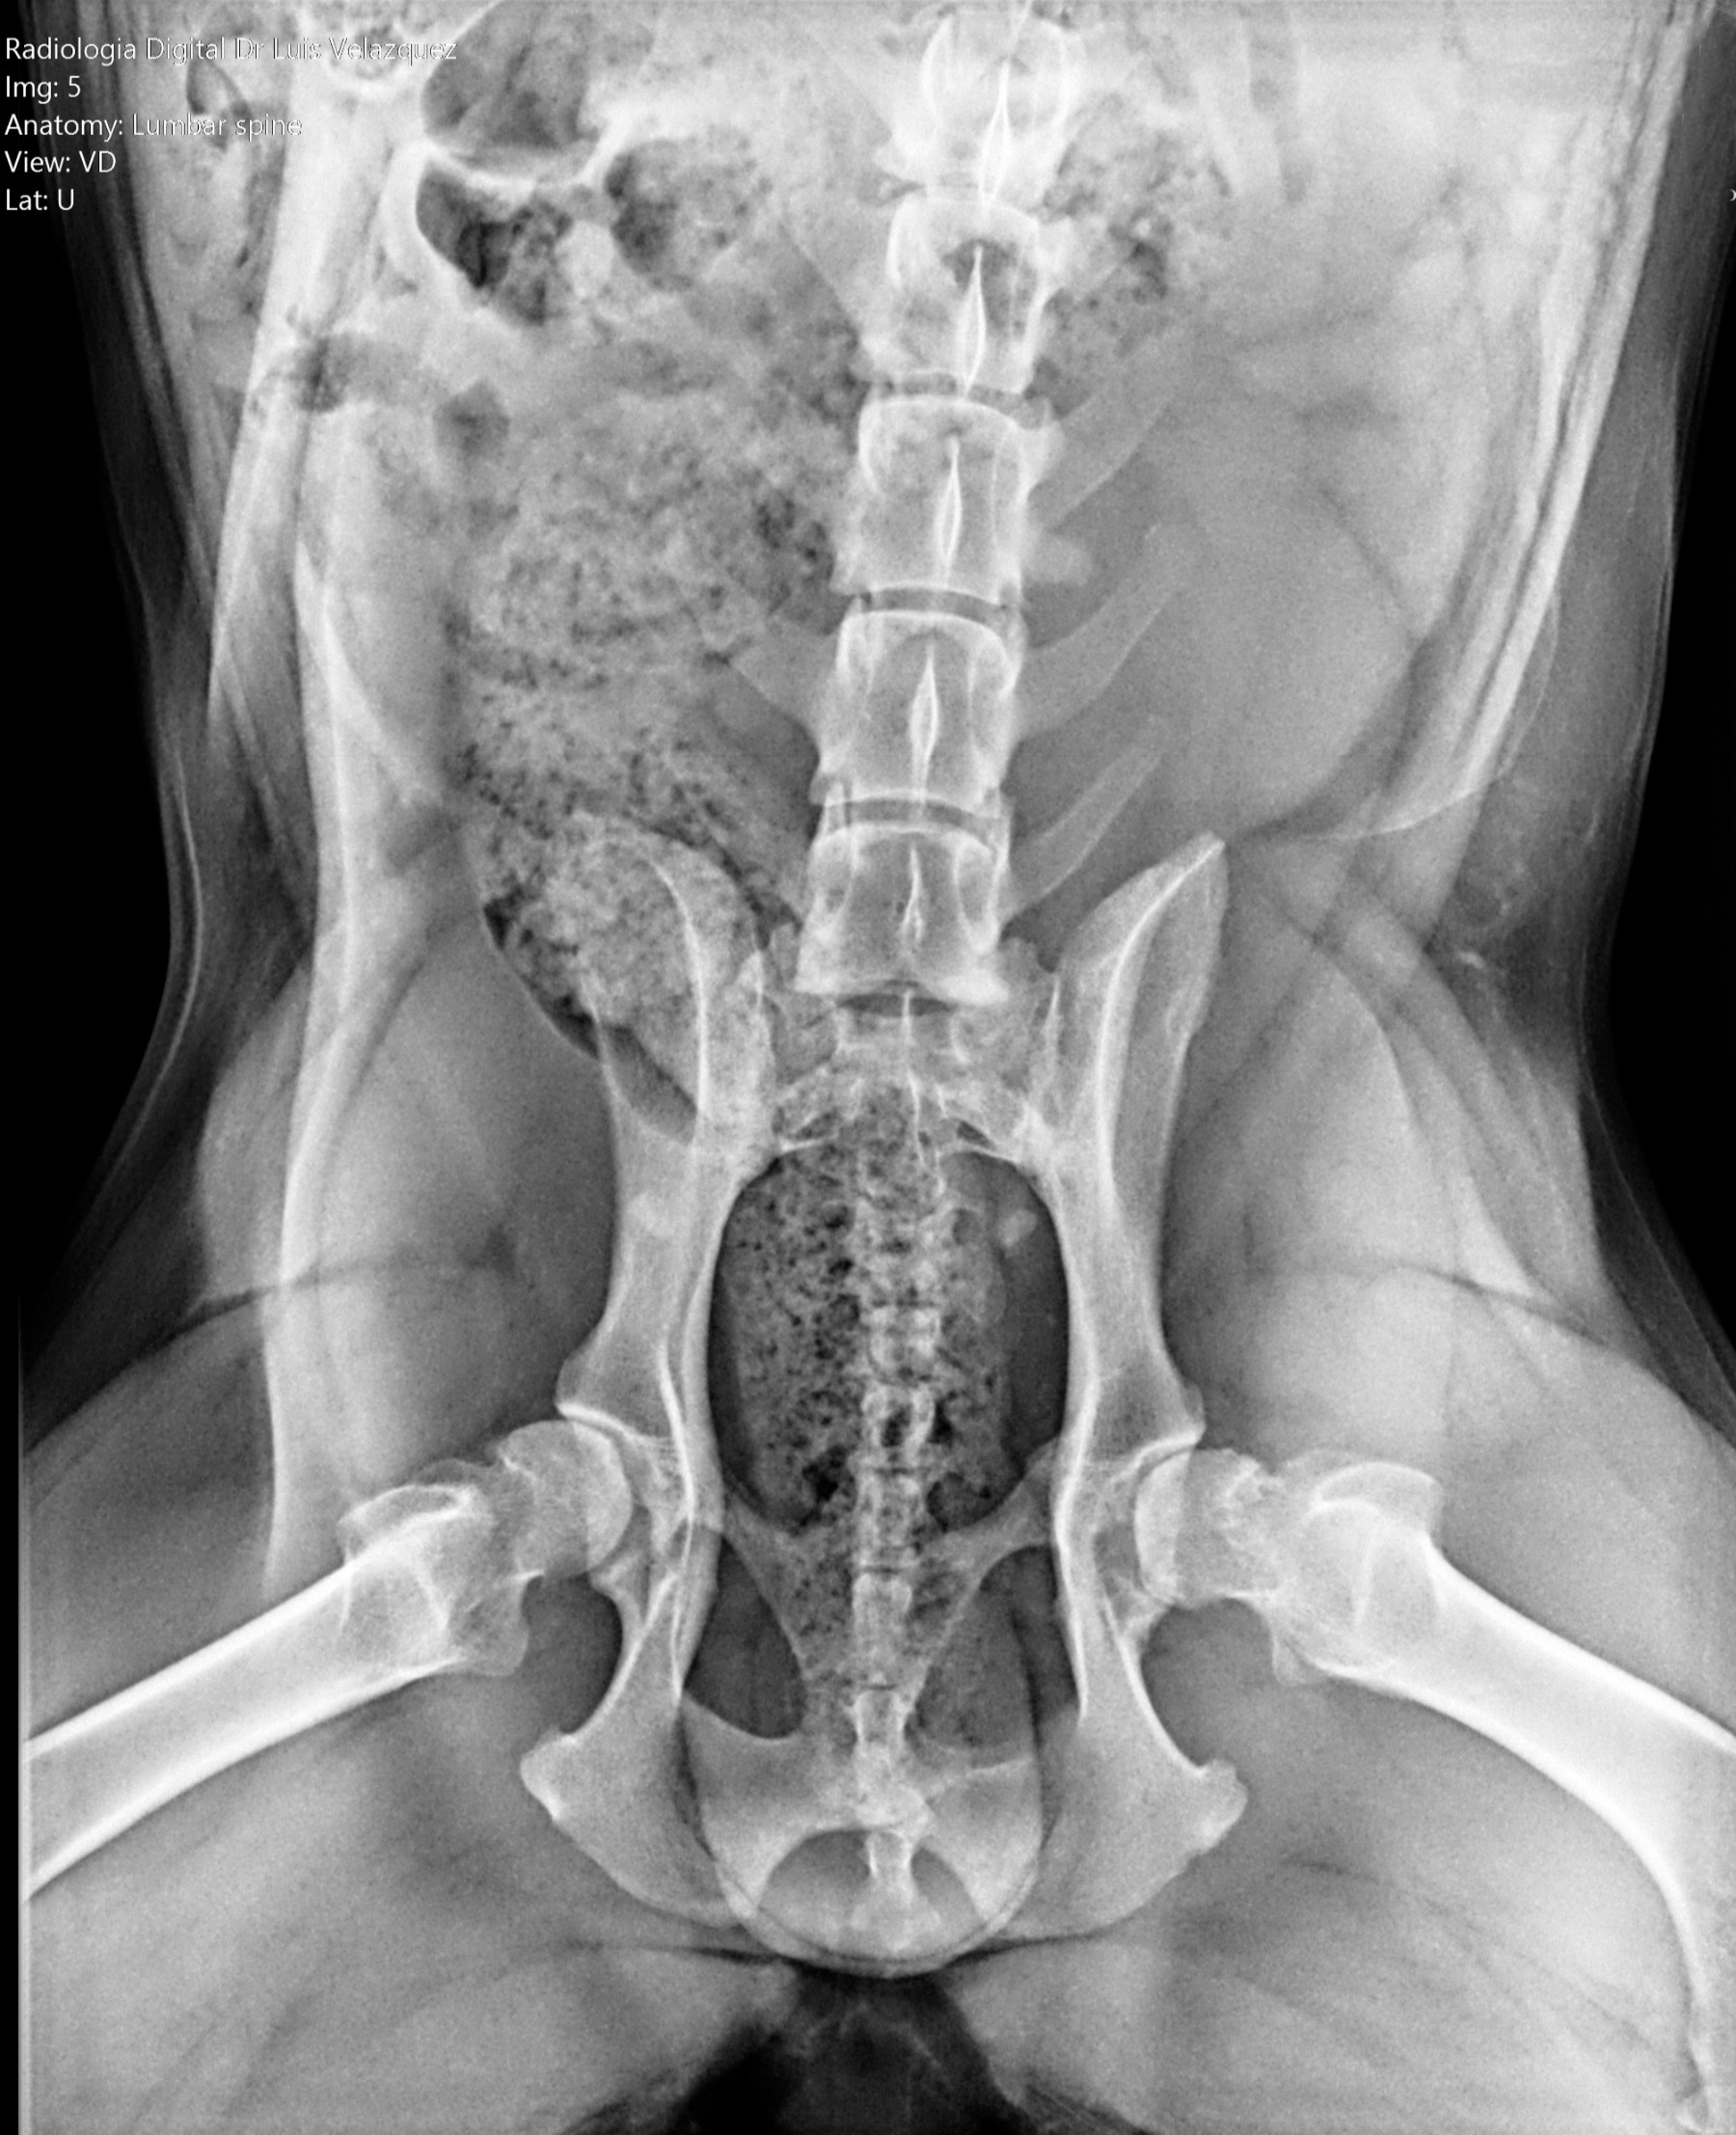

Cambios Térmicos en las Extremidades de Caballos,

Asociados a Golpes y su Evaluación por Termografía.

Los caballos de salto, en competencia, pueden derribar obstáculos y lastimarse. Si se golpean, no siempre claudican. Considerando al calor como un signo de inflamación, se evaluaron los cambios térmicos de 6 áreas de las extremidades torácicas y pelvianas de 23 caballos de salto en nivel de competencia de 1.05 a 1.60 m de altura, por medio de termografía durante 4 días de competencia (N=2208 áreas).